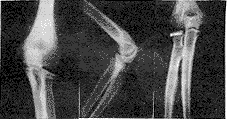

微型螺丝钉治疗桡骨头骨折15例报告

从1990年起,我院在上海手术器械六厂协助下 ......